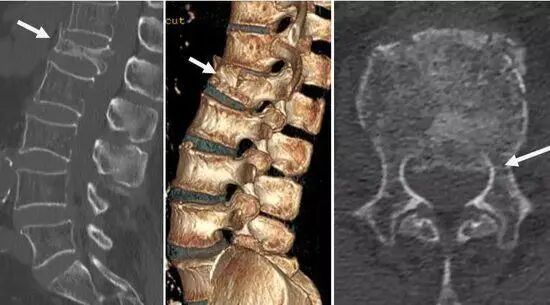

病例:患者李某,83歲,因不慎從樓梯摔落導(dǎo)致腰背部劇烈疼痛,活動(dòng)時(shí)加重,站立及行走困難,診斷為:腰1椎體爆裂性骨折、腰椎椎管狹窄。

微創(chuàng)經(jīng)皮椎體成形術(shù)適用于大多數(shù)嚴(yán)重骨質(zhì)疏松并椎體壓縮性骨折患者。該患者椎體爆裂性骨折,從腰椎CT可看出,該椎體前方、側(cè)方多發(fā)骨折,且椎管內(nèi)存在骨塊壓迫,壓迫椎管將近1/3,單獨(dú)應(yīng)用該術(shù)式,骨折椎體無(wú)法很好恢復(fù)原先高度、易發(fā)生骨水泥泄漏,且后期椎管內(nèi)骨折塊可進(jìn)一步壓迫椎管,造成嚴(yán)重的神經(jīng)壓迫癥狀;微創(chuàng)經(jīng)皮釘棒內(nèi)固定術(shù)主要應(yīng)用于年輕的脊柱骨折患者,該術(shù)式相對(duì)于開放釘棒內(nèi)固定術(shù),具有創(chuàng)傷小、出血少、手術(shù)時(shí)間短等優(yōu)勢(shì)。